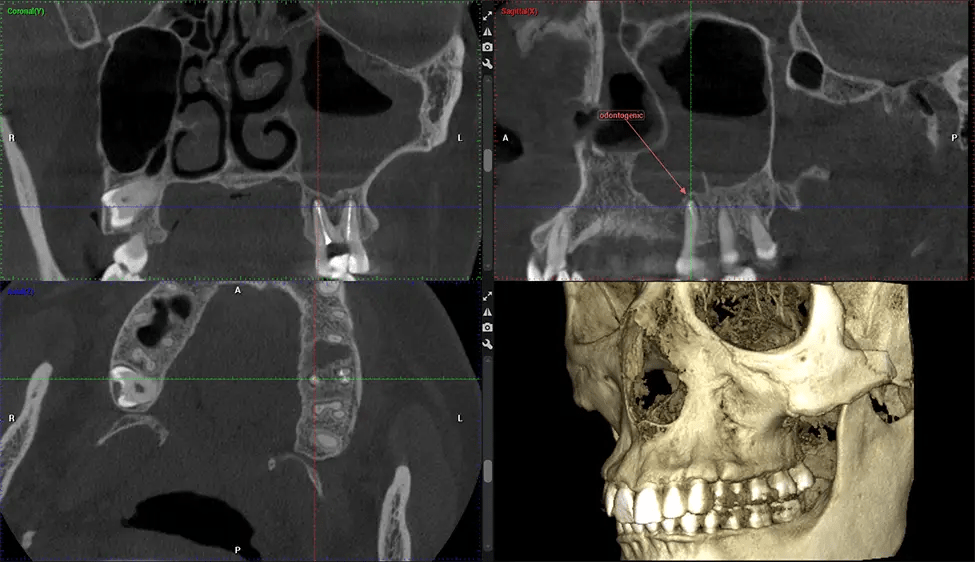

Cone Beam Computed Tomography (CBCT) is an advanced imaging technique used in dentistry and maxillofacial surgery to obtain detailed 3D images of the oral and maxillofacial structures. At Dr G Dental Studio, our CBCT scanners utilize a cone-shaped X-ray beam and a specialized detector to capture images from different angles. A computer then combines these images to create a 3D representation of the patient’s oral anatomy.

This 3D scan, called cone beam computed tomography, gives your dentist a more complete image of your oral anatomy and disease processes than a traditional X-ray. Unlike conventional X-rays, which capture a 2D image of your mouth from various angles, a 3D scan takes multiple digital X-rays for one image. It provides a complete view of your jaw, teeth, nerves, and soft tissues. This enhanced view allows dentists to detect minor issues not visible in traditional 2D scans, such as impacted wisdom teeth or bone fractures in the sinus cavity.

There are many benefits to using CBCT technology, especially compared to the traditional 2D X-ray format. One of the most significant advantages of CBCT scans is that they provide much more information than traditional X-rays. A scan lets your dentist see images from all angles of your jaw and mouth, including your sinuses, nasal cavity, cheekbones, and other surrounding areas. This added information helps your dentist craft a comprehensive treatment plan that addresses all aspects of your oral health.

Another significant benefit is that 3D imaging provides more precise images of your bone structure. These images are more detailed, providing you with a more accurate diagnosis. An accurate diagnosis means better treatment for you.

The patient is first positioned in the CBCT scanner, which typically consists of a rotating arm that houses the X-ray source and a detector. The patient’s head is immobilized to ensure accurate image capture. The X-ray source and detector rotate around the patient’s head, capturing various X-ray images from multiple angles. As the X-ray source rotates, it emits the cone-shaped X-ray beam towards the detector. The detector captures the X-ray images, which are then processed by the CBCT software.

After the scanning process, the captured X-ray images are processed by the CBCT software, which applies algorithms to reconstruct a detailed 3D image of the scanned area. The software compiles these individual X-ray images and creates a digital 3D representation of the patient’s anatomy. The reconstructed 3D CBCT image can be viewed and analyzed by the dentist or radiologist. This image can be manipulated, rotated, and zoomed in or out to examine specific structures and evaluate the patient’s condition.